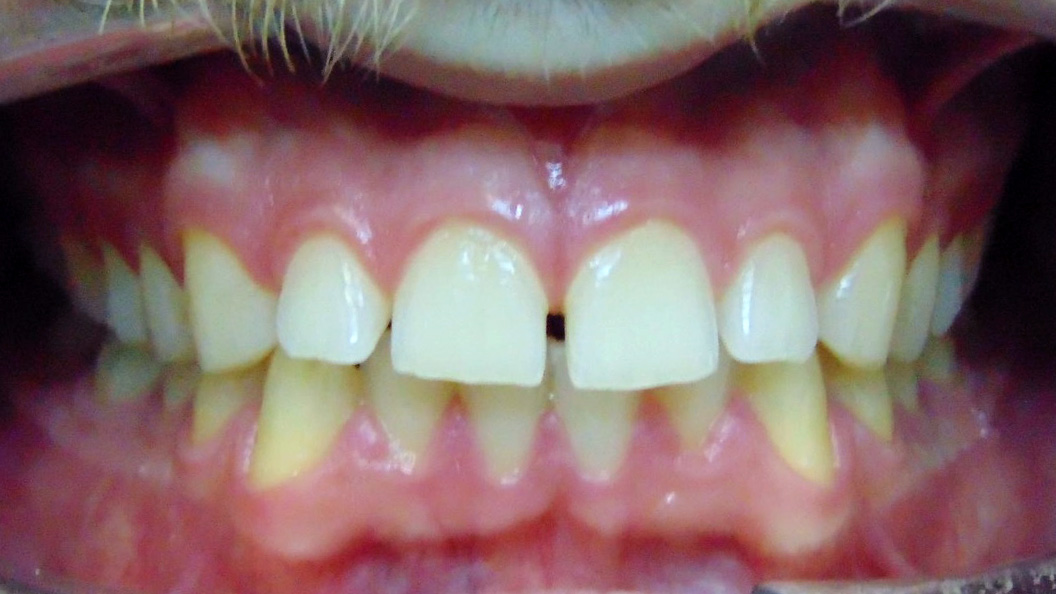

До и после лечения

В «Стоматологию Комфорта» обратился пациент с целью исправления нескольких дефектов прикуса. Проведя осмотр, врач-ортодонт Резниченко Анна Васильевна сделала заключение о наличии диастемы, тремы на верхней челюсти во фронтальном отделе. Также было диагностировано скученное положение зубов на нижней челюсти во фронтальном отделе. Врач принял решение об ортодонтическом лечении элайнерами 3D-smile.